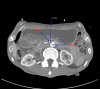

Cast syndrome, commonly known as superior mesenteric artery (SMA) syndrome is a rare cause of small bowel obstruction caused by compression of third part of duodenum from narrowing of the angle between superior mesenteric artery and abdominal aorta resulting in symptoms of duodenal outflow obstruction. A 46-year-old male presented with acute worsening of chronic abdominal pain, nausea and vomiting aggravated with eating. Computed tomography of abdomen and pelvis revealed the dilatation of gastric and proximal duodenum due to compression of third part of duodenum between superior mesenteric artery and aorta. Conservative management with total parental nutrition failed and patient underwent gastrojejunostomy with relief of his symptoms. Cast syndrome is a rare condition but should be kept in mind in patients with abdominal pain, vomiting, early satiety and weight loss. CT abdomen usually reveals the diagnosis but upper GI endoscopy helps to rule out other causes of duodenal obstruction and gastric dilatation.